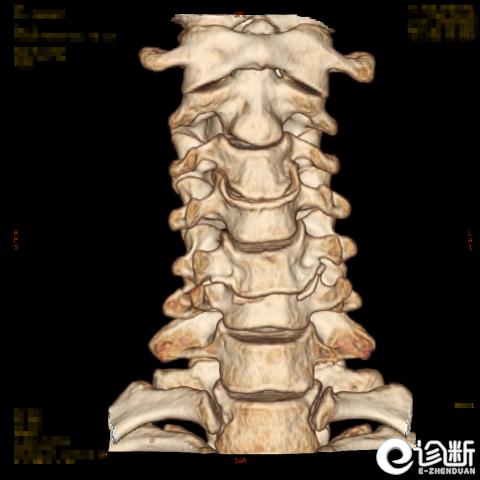

颈椎骨折

CT:显示椎管(骨折碎片可压迫椎管)

分型:

根据骨折的水平及位置:C1-Jeferson骨折:前后弓骨折

C1-侧块骨折

C2-Hangman骨折(峡部):Levine分型

C2齿突骨折1型、2型、3型

C3-7骨折: